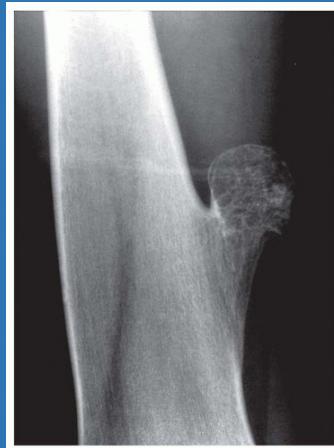

| Compartment Syndrome | Increased pressure within a closed fascial compartment, leading to reduced tissue perfusion, hypoxia, and irreversible muscle and nerve damage. Causes: Fractures (especially tibia/forearm), severe soft tissue trauma, arterial injury, burns, tight casts/dressings, post-ischemic reperfusion swelling, IV fluid extravasation, and bleeding disorders (e.g., hemophilia). High-Risk Notes: Pain may be absent in altered consciousness, children (monitor analgesia response), polytrauma, sedated/epidural cases, or concomitant nerve damage. Open fractures do not always decompress pressure. Gross/Clinical: -tense, shiny leg swelling with blisters in compartment syndrome.Imaging: - Intraoperative fasciotomy | History/Symptoms: Pain out of proportion to the injury (e.g., a “bursting” sensation), which is not relieved by analgesia. Clinical Features (The 5 P’s): - Pain with passive stretch (early, key sign; e.g., ankle dorsiflexion for leg, wrist for forearm). - Paresthesia (early). - Palpable tense swelling (shiny skin, blisters: clear=mild, serosanguinous=severe, bloody=worst; dusky/pallor skin). - Pallor, Paralysis, Pulselessness (late, ominous signs; pulses often palpable until late). Investigations: Primarily a clinical diagnosis (high suspicion key). Compartment pressure measurement can confirm: absolute pressure >30 mmHg or Delta Pressure (Diastolic BP - Compartment P) ≤ 25 mmHg. | Initial: ABCs, supplemental oxygen. Remove all circumferential dressings, casts (bivalve to skin), and splints. Elevate the limb to heart level (not above; higher reduces inflow). Correct any hypotension. Surgical: Urgent Fasciotomy if no response within 1h or confirmed pressure (prophylactic in high-risk like major osteotomy). Release all compartments/skin with long incisions; debride necrotic muscle via 4C’s (early: pink/red, soft, contracts/bleeds on pinch; late: dark, firm, no response); preserve neurovascular. Wound open (bulky dressing/splint, VAC, or boot-lace gradual closure); repeated inspections x48h; coverage in 3-5 days (skin graft usual; flap if nerves/vessels/bone exposed). | Cellulitis, Deep Vein Thrombosis (DVT), Arterial occlusion, Severe soft tissue injury without compartment syndrome; equivocal cases in polytrauma. | Complications: Volkmann’s ischemic contracture (permanent deformity, weakness, sensory loss, chronic pain). Contraindications (Fasciotomy): Confirmed >48h (irreversible damage, high infection risk from dead tissue); crush injuries with already necrotic muscle. |

| Open Fracture | A fracture with a breach in the overlying skin and soft tissues, creating communication with the external environment. All open fractures are considered contaminated (even small punctures; aka compound fracture). Causes: Can result from high-energy trauma (RTAs, falls, firearms; signs: degloving, crush syndrome, bone loss, segmental) or low-energy trauma. Contamination risk higher with farm/soil injuries, bites, delayed presentation (>12h), fecal/oral/soil/water exposure. Mechanism: Low/high velocity missiles (cavitation >300 m/s); in-out (cleaner) vs. out-in (dirtier). Gross/Clinical: ![]() | History: Mechanism of injury (energy, time, place, type/impact method), consciousness, wound size/bleeding amount, other injuries (often missed), tetanus status. Assessment: ATLS protocol (ABCDE) first (treat patient, not fracture; exclude shock/brain injury, monitor vitals; viscera exam: ribs=lungs/liver/spleen, pelvis=bladder/urethra). Examine wound (look/feel/move carefully post-splint), check distal neurovascular status, compartment syndrome. Photograph/remove gross contamination; cover with saline dressing. Classification (Gustilo-Anderson): - Type I: <1 cm wound, clean, minimal soft tissue. - Type II: >1 cm wound, moderate soft tissue (no stripping). - Type IIIA: Extensive soft tissue damage, but adequate bone coverage. - Type IIIB: Extensive soft tissue loss with periosteal stripping; bone exposed, requires flap coverage. - Type IIIC: Any open fracture with an arterial injury requiring repair. | Initial (ER): ATLS first. Cover wound with sterile saline-soaked dressing, splint limb, IV fluids (request blood if needed); traction if no distal pulse/deformity. Prophylaxis: Tetanus prophylaxis/serum and broad-spectrum IV antibiotics immediately (culture tissue/blood); clean major contamination. Surgical: Urgent debridement/irrigation within 6-12h (“Dilution is the solution to pollution”; pulse-irrigate 3-6-9L saline; excise non-viable tissue/foreign material, trim skin edges, remove dead muscle/detached bone, preserve N/V). Stabilization: external fixator (preferred severe; replace with cast post-infection); internal if clean/minimal. Wound closure delayed (primary if small/clean; secondary if contaminated/large). Early soft tissue cover. | The diagnosis is typically obvious. Key: Classify severity; identify associated injuries like compartment syndrome, vascular damage, or high-energy signs (e.g., crush). Differentials for contamination: Primary (field debris) vs. secondary (post-fixation if poor debridement). | Complications: Infection (cellulitis, osteomyelitis, chronic with sequestra/drainage, gas gangrene), tetanus; higher with delay/exposure/bites. - embolisms fat, thrombi others.. Case Insight: Unconscious patient (e.g., open tibia post-RTA): ABCDE/cervical collar, distal pulses/traction, admit for debridement; ankle fall: Splint post-ABC, assess neurovascular. |